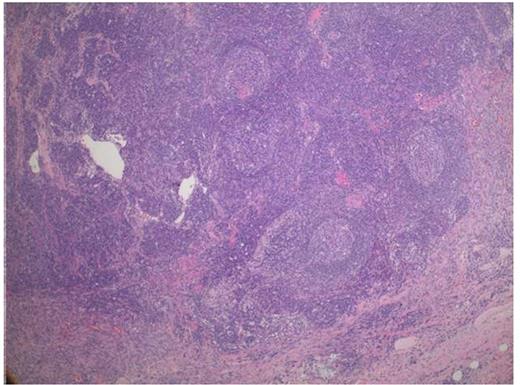

Low power (5X magnification) showing targetoid pattern of follicles and prominent interfollicular stroma with prominent capillaries consistent with Castleman's and a spindle cell proliferation towards the bottom consistent with Kaposi Sarcoma

Higher magnification (10X) shows a prominent follicle with concentric layering of peripheral lymphocytes that resembles onion-skin. To the right, the KS shows spindle cells forming slits with extravasated red blood cells.